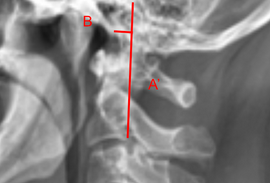

Image Type Cervical Spine X-Ray CT Scan MRI Scan Atlantodental Interval (ADI) Basion-Axial Interval Basion-Dens Interval (BDI) C2 Tilt C2–C7 Coronal Cobb Angle Cervical C2-7 lordosis C2-C7 Translation Chamberlain’s Line / McGregor’s Line Flexion-Extension George’s Line (Posterior Cervical Line) K-Line Interpedicular Distance (IPD) Occiput-C2 Angle Occipital Condyle–C1 Interval (CCI) Posterior Atlantodental Interval (PADI) Power’s ratio Sagittal Canal Diameter Sagittal Vertical Axis (SVA) Spinolaminar line Swischuk Line T1 Slope Torg/Pavlov Canal-to-Body Ratio